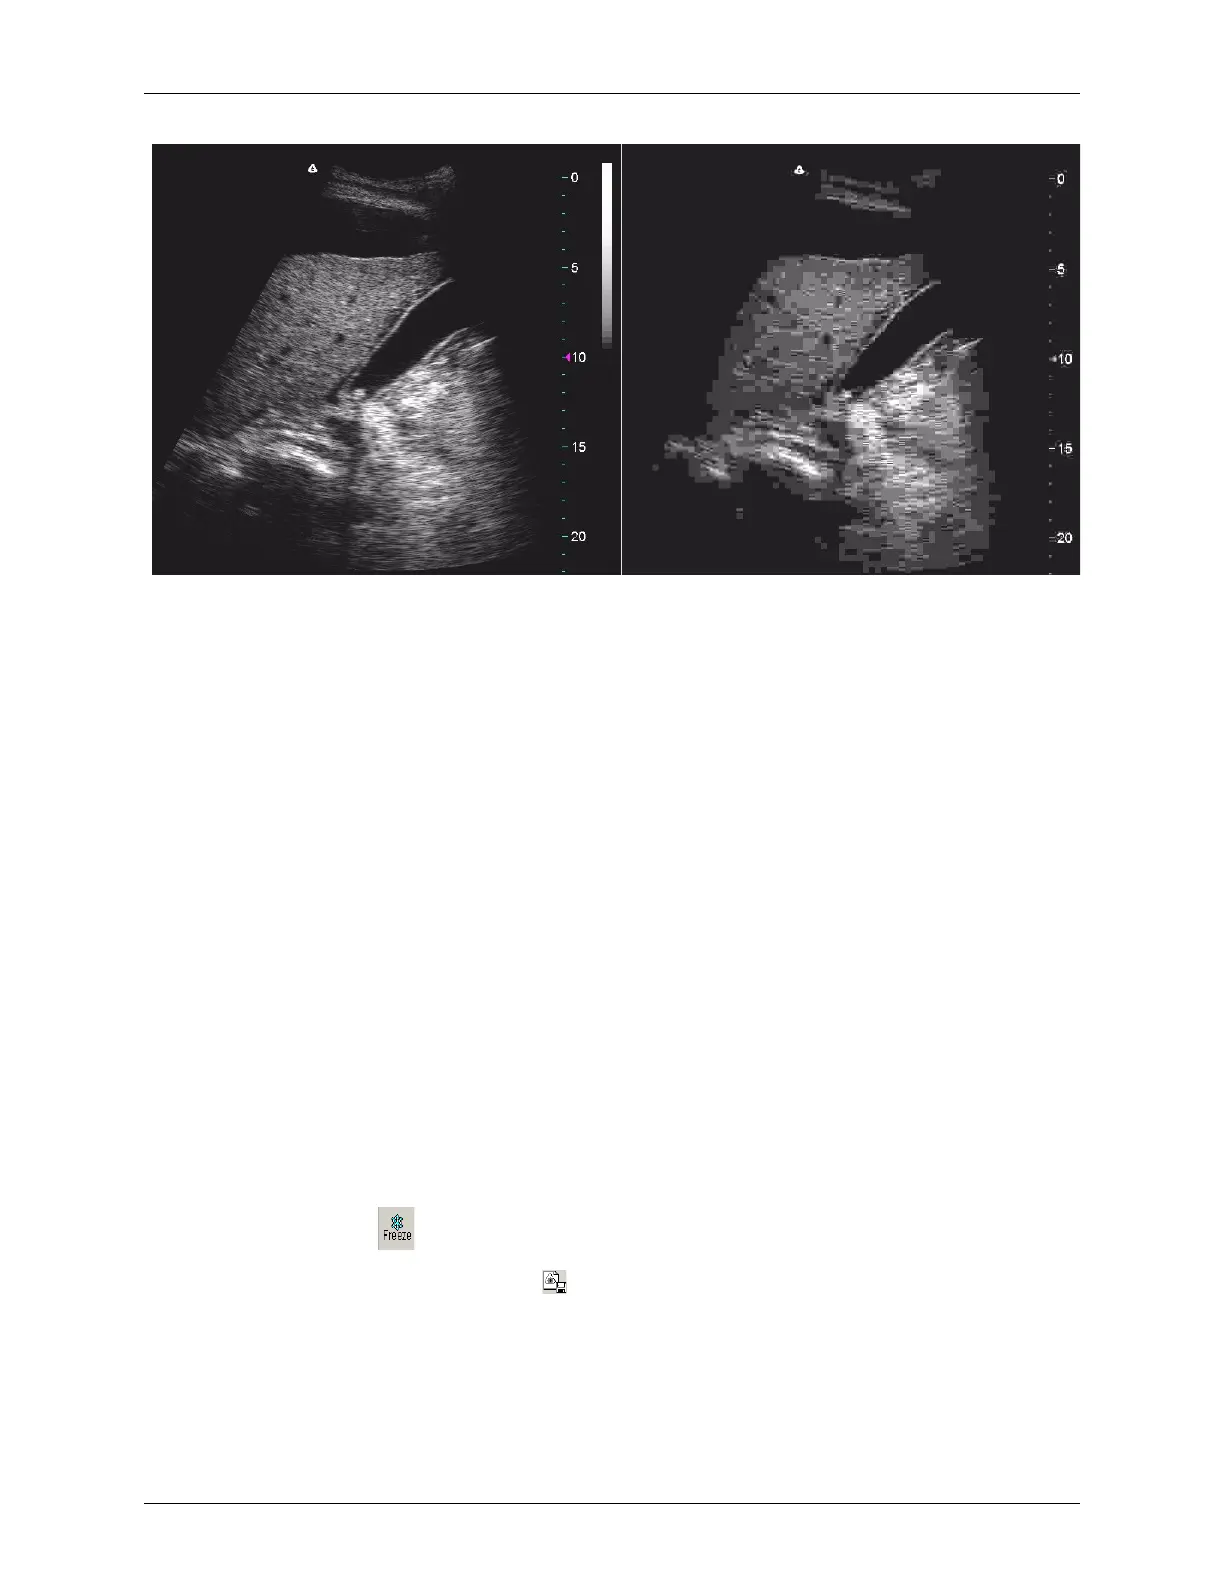

Scan Uncompressed (Left) and JPEG Compressed (Right)

The compressed scan shows squares throughout. If you see squares like these, or an

occasional block, interpret them as JPEG artifacts.